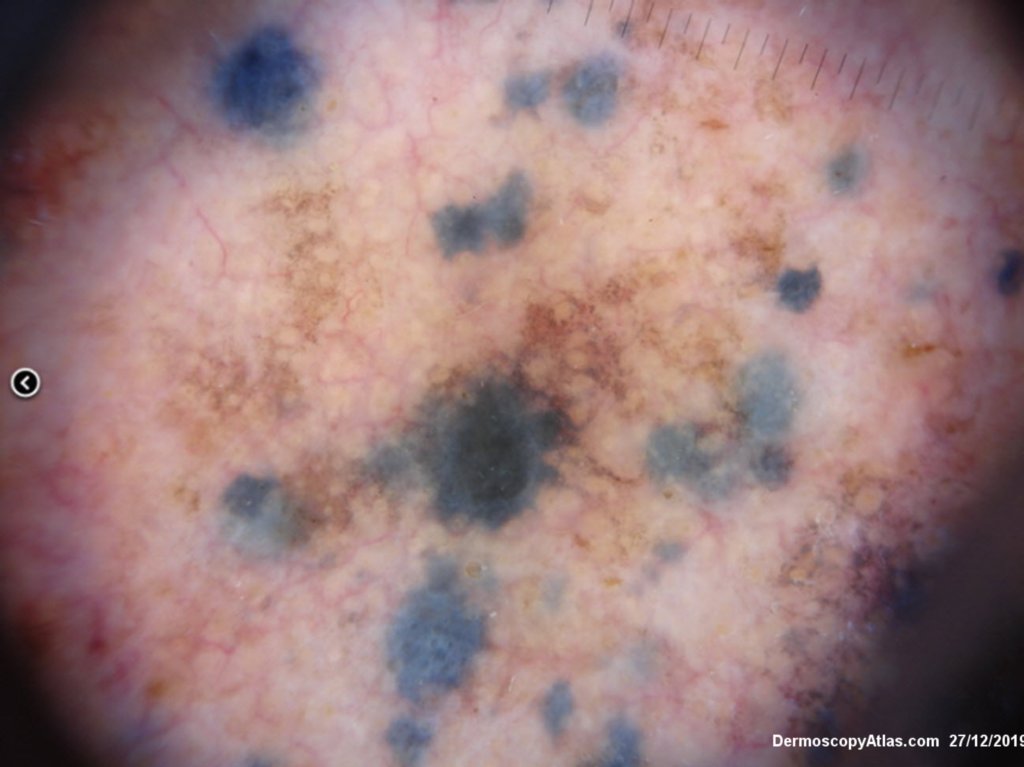

Description: Background brown lesion with blue macules and papules developing

This elderly man had a preceeding lentigo maligna but subsequently developed in transit metastases as shown by the blue macules and papules on his cheek. He was treated with Keytruda. PET scan was negative for spread elsewhere.